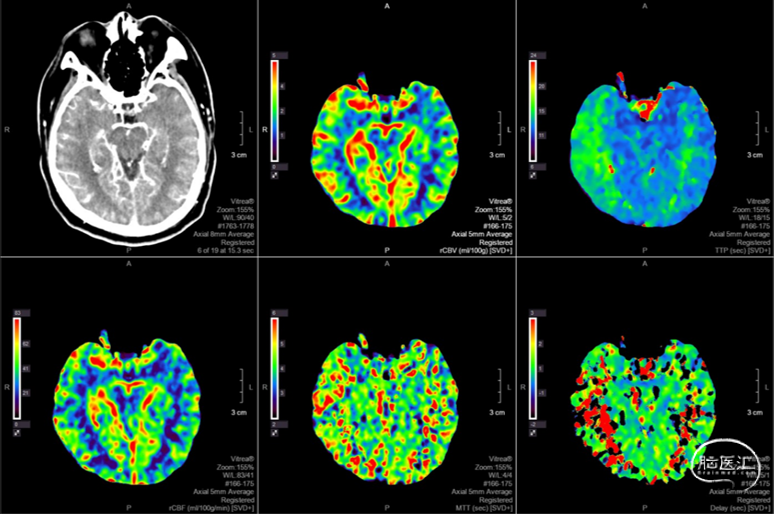

头颅CTP:右侧大脑中动脉区域明显低灌。